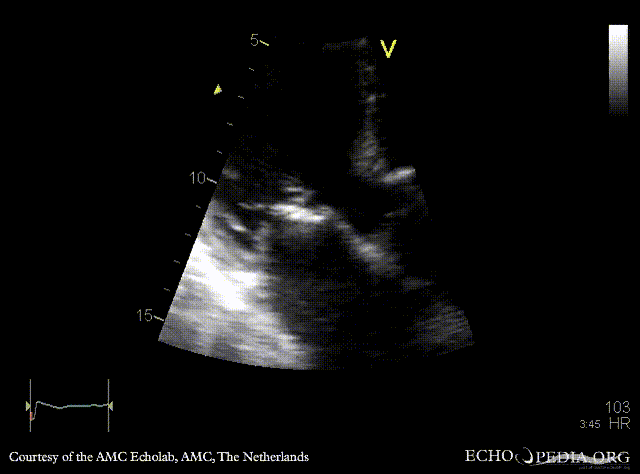

Endocarditis of mitral valve

A5CH A5CH: Color doppler, severe mitral regurgitation